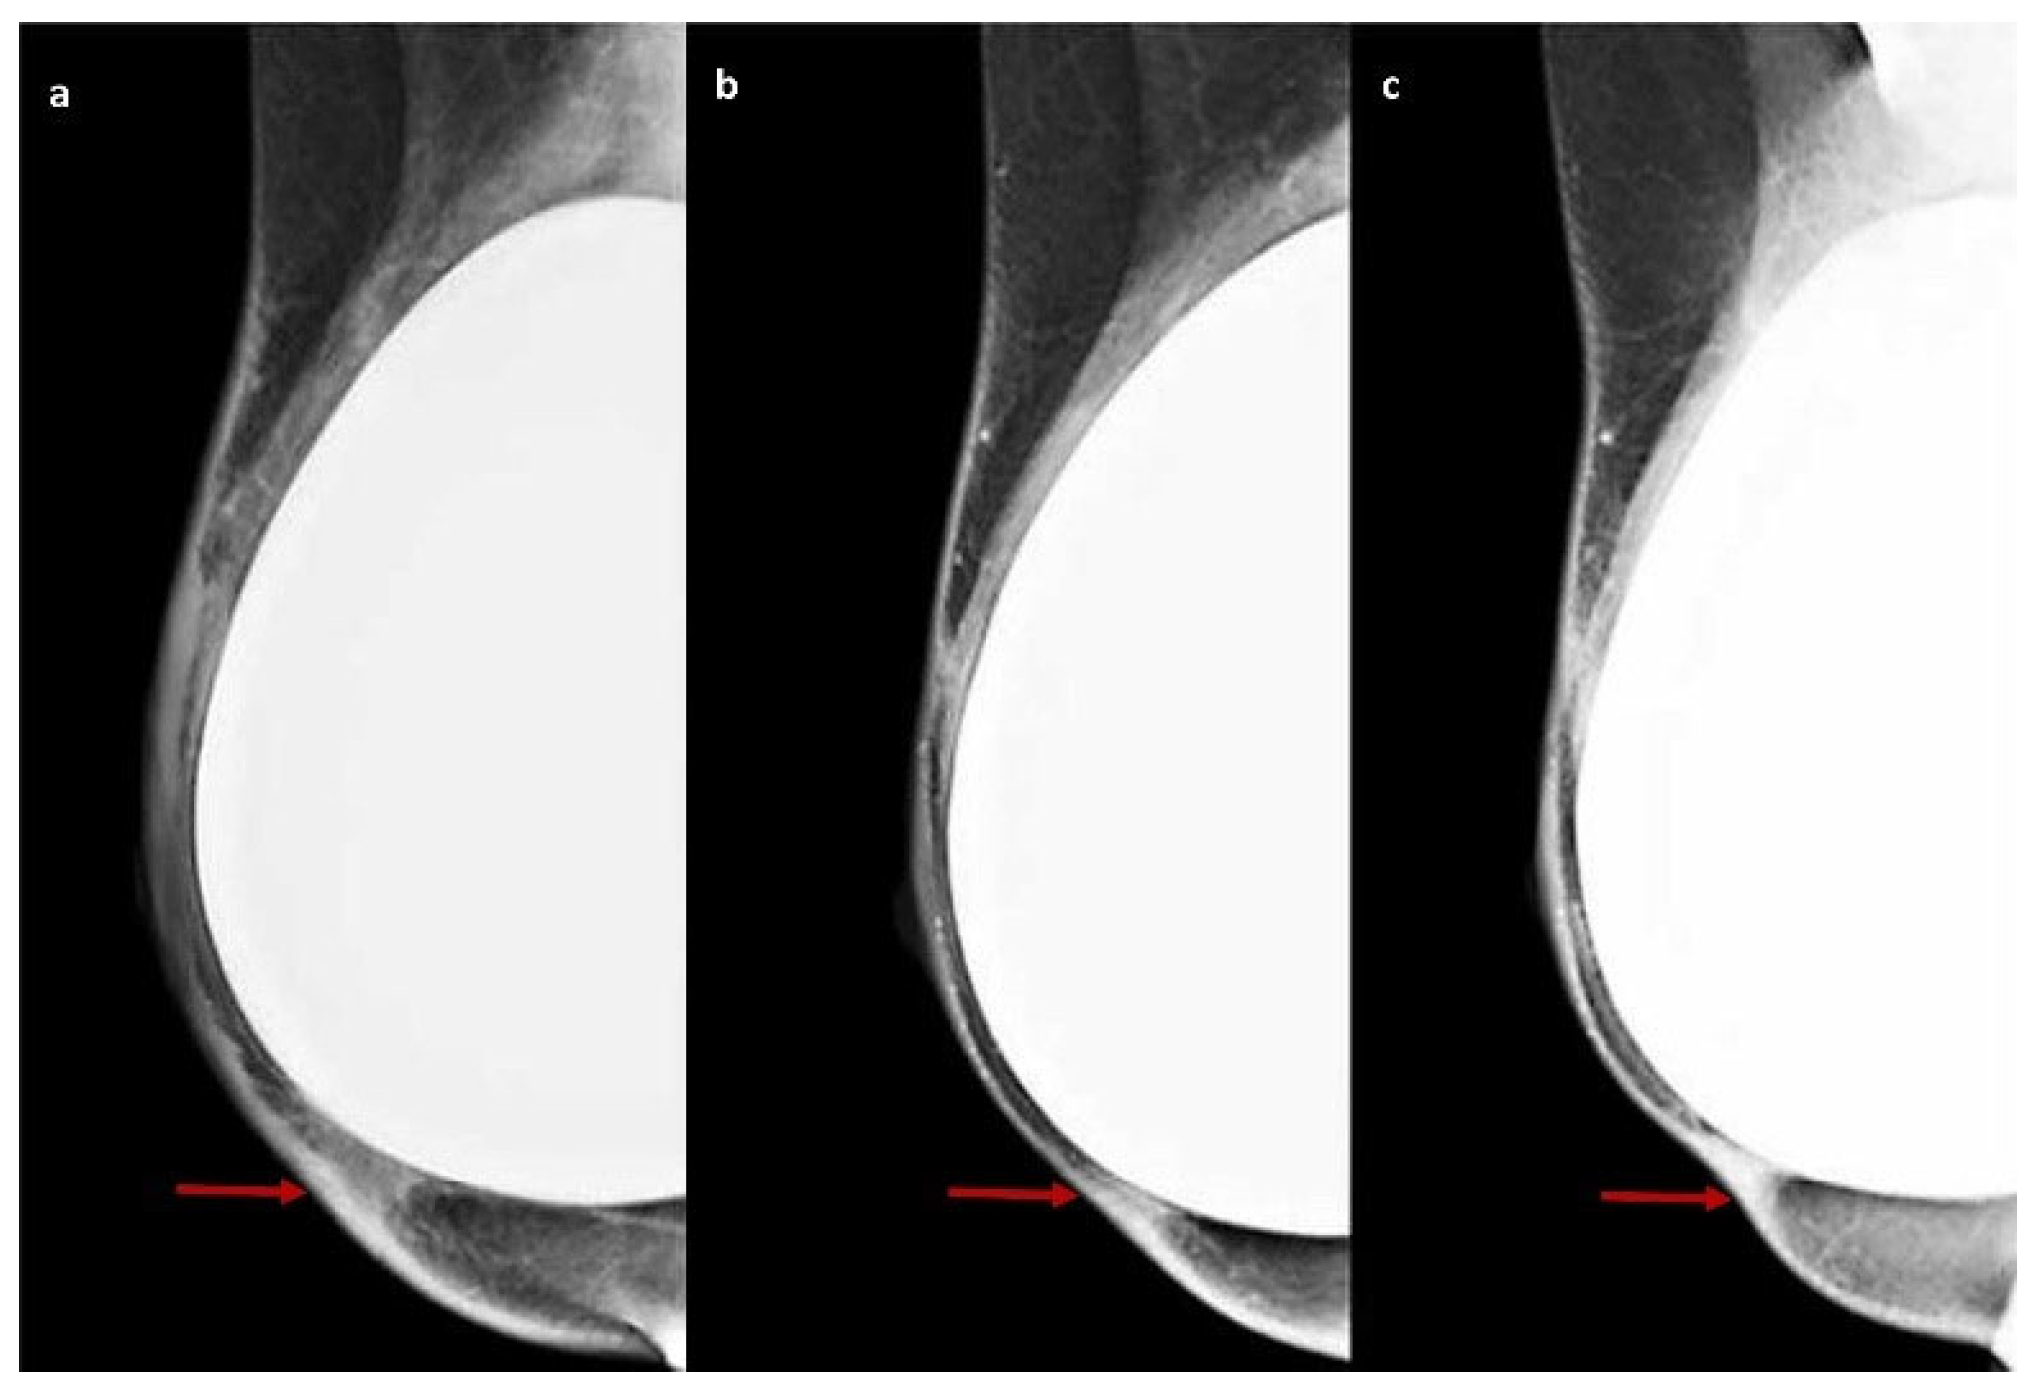

4.1. DM Features of ADM

| DM | Derived from pig dermis | Two patients (3%) | One patient (2%) | Zero patients (0%) | Radiological signs visible on DM completely disappear at T2 |